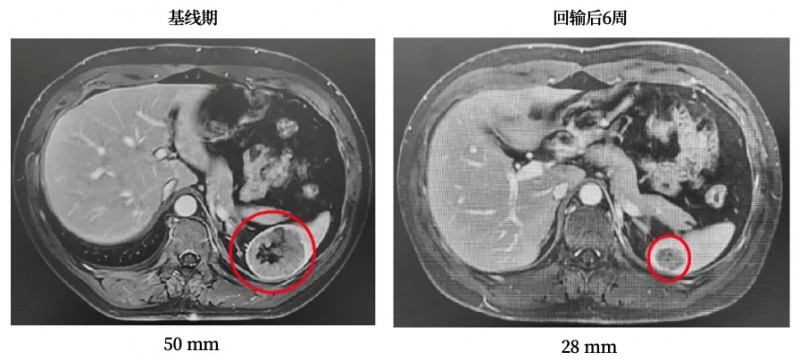

案例2:晚期肺腺癌患者24周无额外治疗病灶持续缩小

一名晚期肺腺癌患者合并淋巴结、胸膜及骨转移,放疗联合靶向治疗后病情仍进展,入组接受GC101细胞回输治疗。疗效评估结果振奋人心:回输后第6、12、18、24周影像学检查显示疗效递进显现,第二次增强CT即见靶病灶缩小36%(详见下图),最终达到部分缓解(PR);更惊喜的是,患者在回输后24周内未接受任何其他治疗,肿瘤病灶仍持续缩小,充分印证了GC101持久的抗癌活性。

▲图源“JUNCELL”,版权归原作者所有,如无意中侵犯了知识产权,请联系我们删除